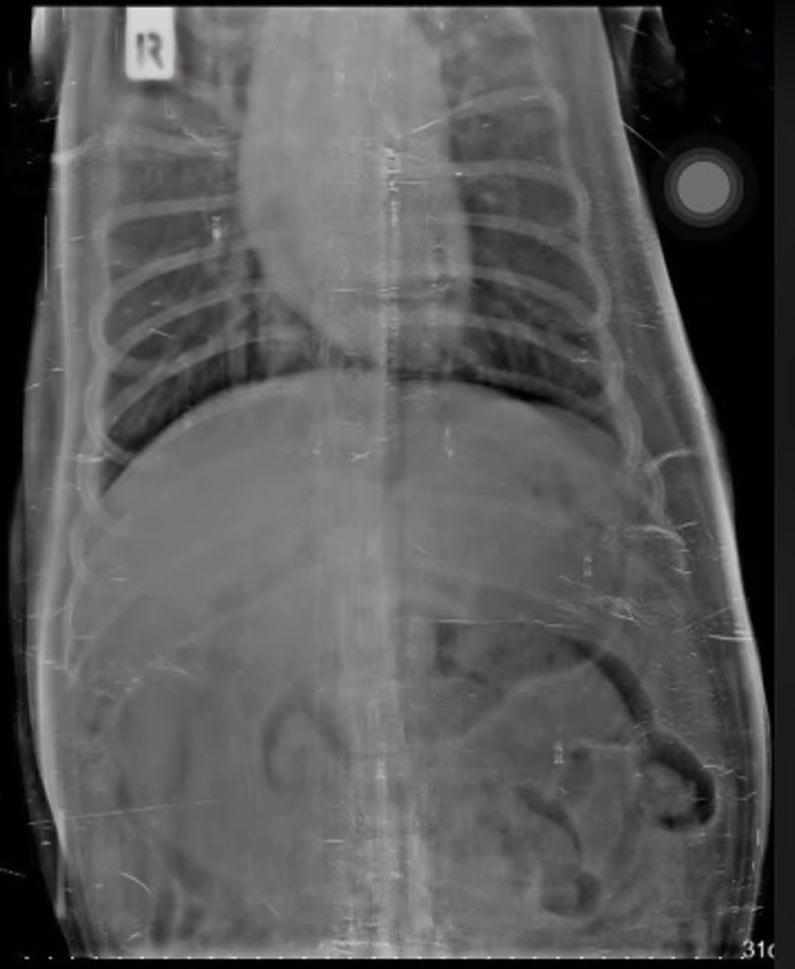

從影片可見,Mo吞下2隻幼龜後變得沒精打采,肚子脹脹,遲遲未能排便。獸醫檢查後發現Mo的腸道發炎,但因為在這些情況下不適合動手術,加上Mo年紀大,若開刀恐有生命危險。因此,醫生決定讓牠住院觀察3天,希望能透過自然排便,排出異物,否則就要冒險開刀。

經過一晚觀察,獸醫發現Mo腸胃內的氣體明顯減少,排泄物亦已移動到腸道末端,顯示腸道阻塞的情況有改善。醫生解釋,龜殼就像雞骨或牛骨,若能順利排氣並有排便力道,有機會自然排出。

幸好經過幾天,Mo的情況逐漸好轉,不僅能排出部分排泄物,腸胃氣體也明顯移動,沒有嘔吐,也能正常進食,顯示腸道未有阻塞。主人仍不放心,將X光片給其他獸醫會診,結論是暫時不需動手術。目前Mo情況穩定,但龜殼仍卡在腸道內,要等牠慢慢排出,獸醫也給牠吃消化藥。